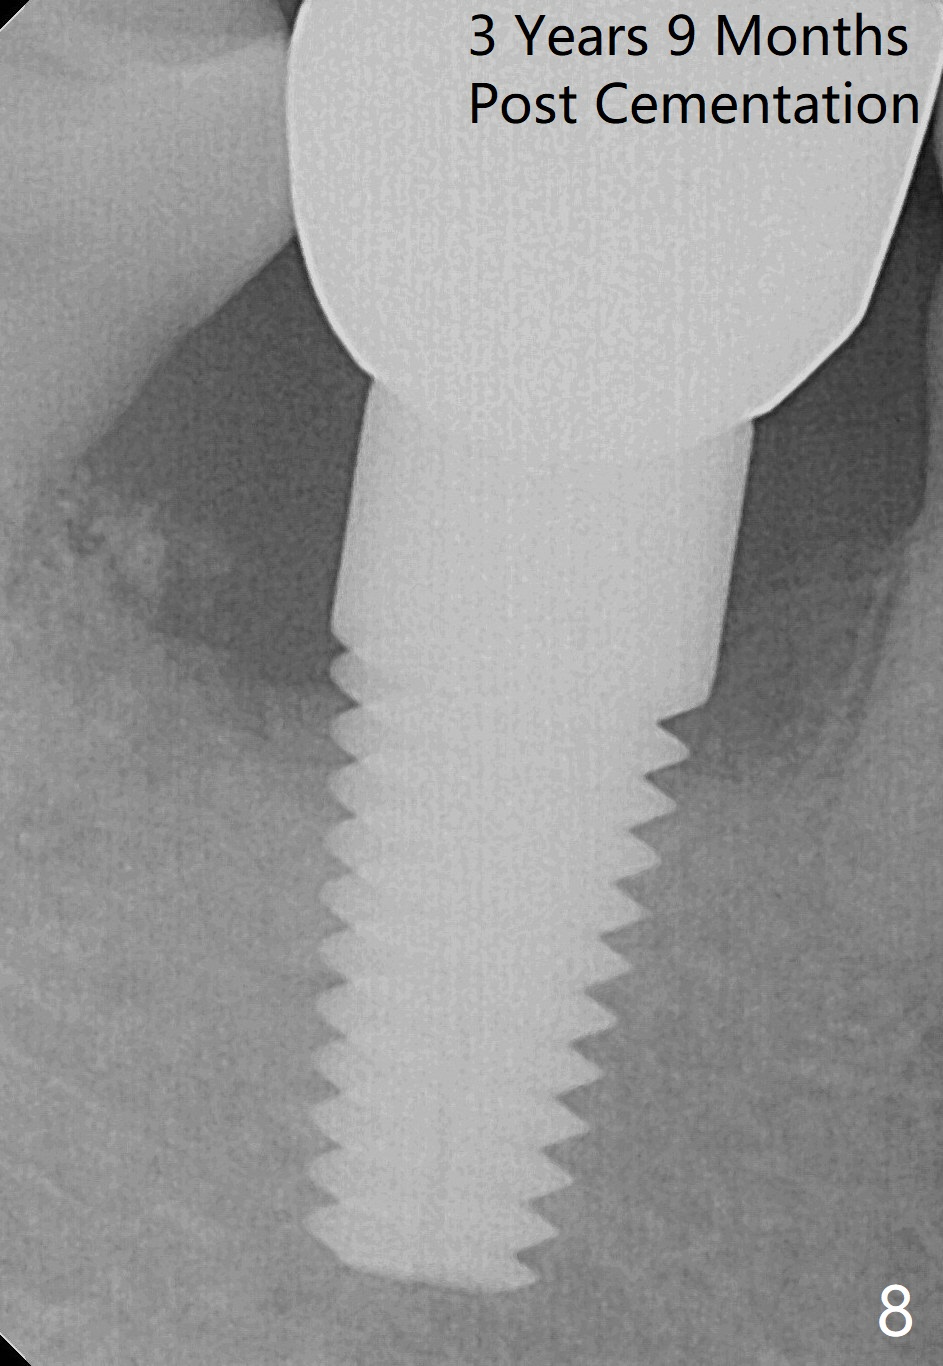

Three months and 3 weeks later, there is bone contacting the coronal 1st three threads of the implant (Fig.7 white >). It would be safe to predict that the bone will meet the bone indicated by red arrowheads to form the distal socket in the near future. The mesial defect appears to have been repaired 3 years 9 months post cementation (Fig.8). The7x17 mm implant is placed lingually enough (Fig.9). It should be 2 mm more apically.